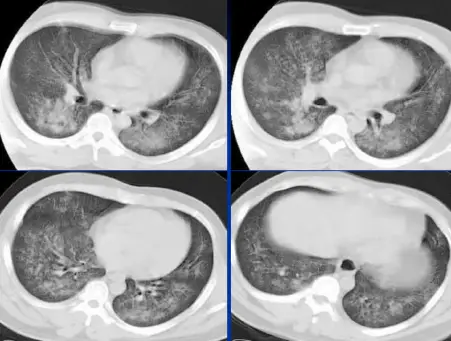

病例:男,28岁,溺水肺水肿,溺水1小时,咳嗽,呼吸困难,咳粉红色泡沫样痰,肺部听诊大量湿啰音。

CT表现

肺泡性肺水肿:两肺透光度减低,并见广泛性分布结节样、斑片样密度增高影及毛玻璃样影,以两肺内、中带分布较明显,右侧较左侧多。